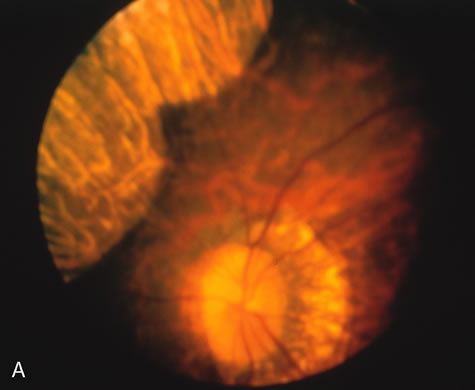

In retinitis pigmentosa (RP), the pigment abnormalities of atrophy, migration, and clumping are made apparent by transmitted hyperfluorescence and blocked hypofluorescence (Fig. 1A). Patients who have very minimal pigmentary alterations (pauci pigmentary RP) or no pigment abnormalities (RP sine pigmento) may show the abnormalities on fluorescien angiography (FA). It is uncommon to see choriocapillaris atrophy except in the late stages. This finding corresponds to the histopathology, which shows that the earliest abnormalities are in the photoreceptors and that the choroid is normal.1

Dye leakage in RP may occur from the retinal vessels or at the level of the retinal pigment epithelium (Fig. 1B).2–4 The leakage may be seen in the macula and posterior pole, along the vascular arcades in the distribution of the radial peripapillary capillaries, and in the periphery (where an exudative vasculopathy resembling Coats' disease is suggested).